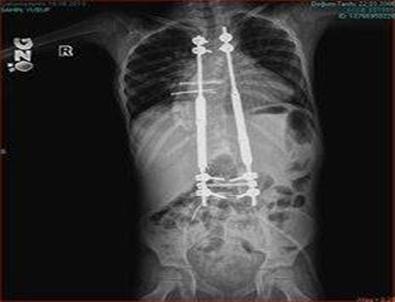

Skolyoz (omurga eğriliği) hastalığı tedavisinde geliştirilen yeni ameliyat tekniğinin, Karadeniz'de “ilk kez” Medical Park Samsun Hastanesi’nde uygulandığını söyleyen Prof. Dr. Nedim Karaismailoğlu, “Medical Park Hastanesi’nde skolyoz (omurga eğriliği) tedavisi gören 7 yaşındaki Yusuf Şahin, Türkiye'de yeni yapılmaya başlanan, omurga eğriliği için yeni geliştirilen ameliyat tekniği ile operasyona alındı. 4 saatlik bir operasyon ile 20 cm uzunluğunda ‘uzayan platin’ adı verilen bir alet takıldı” şeklinde konuştu.

Bu tekniğin Türkiye'de son 6 aydır uygulandığını ifade eden Prof. Dr. Nedim Karaismailoğlu, “Bu yeni yöntem çocuğun büyümesine ve eğriliğin giderek azaltılmasına müsaade ediyor. Tekrar ameliyata gerek olmadan 3 ayda bir hasta geliyor. Ameliyat yapılmadan bir makine yardımı ile içteki parçanın uzaması sağlanıyor ve çocuğun konforu artıyor. Bu yöntem, hastalar için umut ışığı oldu" ifadelerini kullandı.